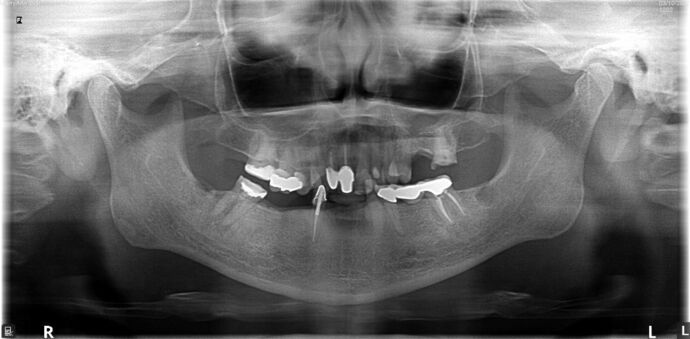

All-on-4/ Full Mouth Dental Implants / Teeth in a Day: Case 20-Gummy smile and failing teeth treatment with Upper and Lower All-on-4 Bridges

This high school teacher was embarrassed about losing her teeth one at a time and had multiple infected teeth causing her pain. She was also unhappy with her gummy smile and found Dr Bidra online. She was informed by 2 other dentists that her gummy smile could not be corrected by dental implants. Dr. Bidra was able to successfully accomplish all her treatment goals by extracting all her teeth and installing Upper and Lower All on 4 implant bridges

Procedures : extractions, gummy smile, new implants, All on 4 , Teeth in a day, no bone grafting and full mouth reconstruction with monolithic zirconia bridges.